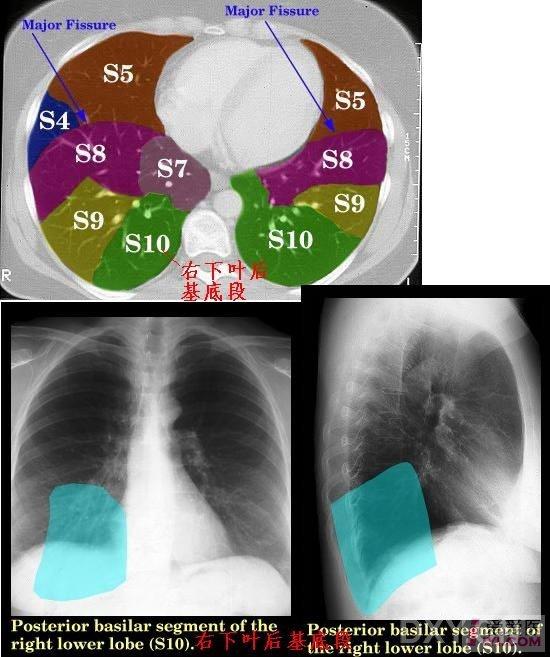

ct肺段定位口诀

如何在ct上区分肺叶和肺段

下图是肺段的解剖彩图.肺段切除就是切除肺叶中间的一个段.